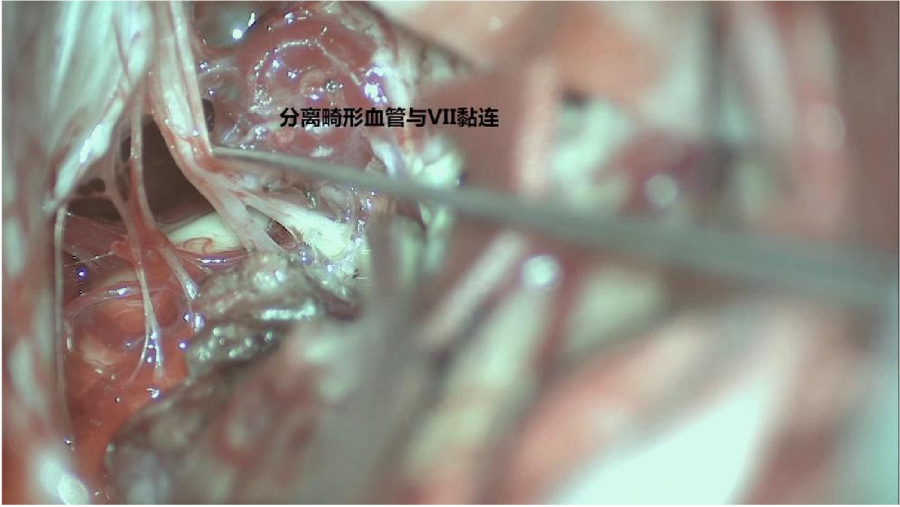

⾏左侧远外侧⼊路脑⼲⾎管畸形切除术,术中所⻅:

3、脑⼲动静脉畸形⼿术切除是注意辨别供⾎动脉与引流静脉,其往往不似其他部位的动静 脉畸形,有叫粗⼤的引流静脉。术中如果不能辨清各⾎管来源与去处,往往会造成不可估量的损失。